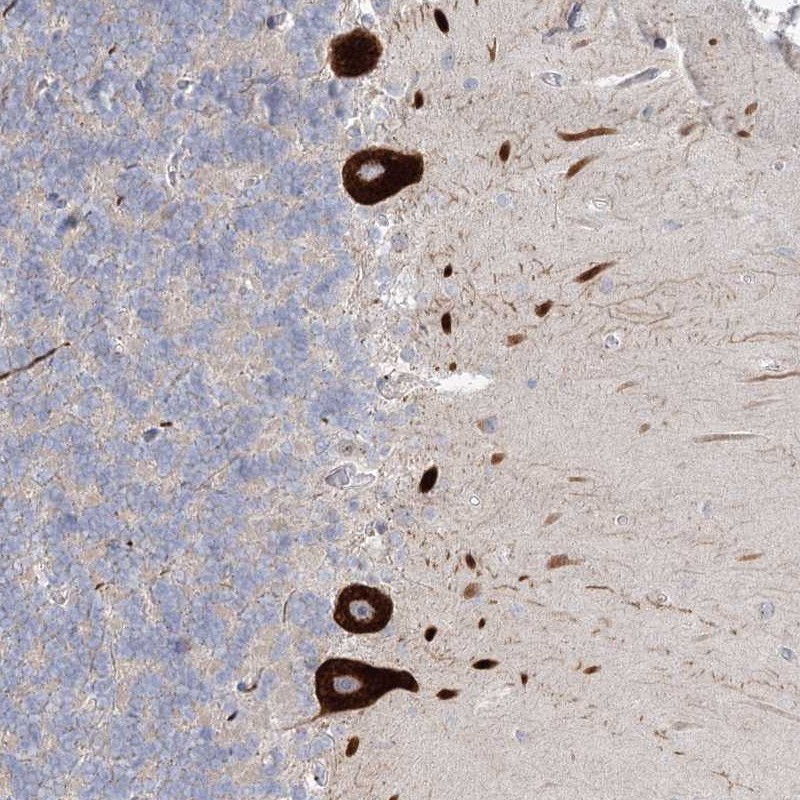

Immunohistochemical staining of human cerebellum shows strong cytoplasmic positivity in Purkinje cells.